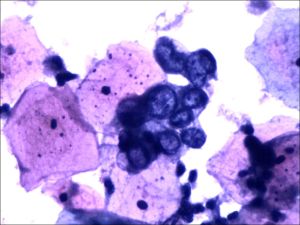

宮頸脫落細胞學檢查圖片方式:①直接塗片是將新鮮標本直接塗在載玻片上。②間接塗片是將各種液體標本(如生理鹽水或運送培養基)進行濃縮處理後再塗片,適用於細胞少的標本。若標本中有凝塊,宜採用細胞塊或傳統組織學方法進行處理。滲出液、灌洗液和尿液等標本不易黏附在載玻片上,宜採用蛋白質(如牛血清清蛋白)或離子類(如多聚賴氨酸)黏附劑,增強細胞和載玻片之間黏附力,最大限度的保存標本中所有細胞。

許多用於組織切片的染色方法也適用於細胞病理學塗片。不同染色技術均適用於婦科或非婦科標本的永久性染色。巴氏染色法適用於濕固定塗片。蘇木素和伊紅染色法(HE染色法)是組織切片最常用的方法,也是許多細胞病理學實驗室常用的染色方法。其他常用染色方法有組織細胞化學染色,如過碘酸Schiff染色、三色染色、Zie-hl-Neelsen染色、Gram染色和Grocott碘化銀染色和有助於識別微生物或鑑別腫瘤細胞分化程度的免疫細胞化學染色等。 ①巴氏染色特點:是細胞具有多色性的染色效果,色彩多樣且鮮艷。塗片染色透明性好,細胞質顆粒分明,細胞核結構清晰。如鱗狀上皮完全形化細胞胞質呈桔黃色;不完全形化細胞胞質呈粉紅色;而角化前細胞胞質呈淺藍色或淺綠色。適用上皮細胞染色或陰道塗片中觀察女性激素水平對上皮細胞的影響。此方法的缺點是染色程式較複雜。 ②蘇木素-伊紅染色法(hemotoxylin-eosin,H-E)染色特點:透明度好,細胞核與細胞質對比鮮明,染色效果穩定。細胞質染成淡玖瑰紅色,細胞核染成紫藍色。紅細胞染成朱紅色。染色步驟簡便,適用於痰液塗片。③瑞氏-吉姆薩染色法(Wright-Giemsastaining)特點:細胞核染色質結構和細胞質內顆粒顯示較清晰。此方法多用於胸腹水、前列腺、針吸細胞學及血液、骨髓細胞學檢查。操作簡便。